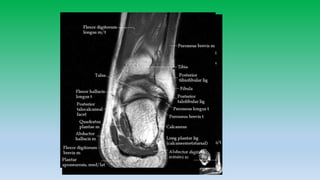

Medial ankle tendons:

• Tibialis posterior attaches to navicular , cuniform and base of 1st-4rt

metatarsal. Tibialis posterior tendon provides support to longitudinal

arch of foot and injury can cause flat foot.

• Flexor digitorum longus passes lateral to tibialis posterior tendon and

inserts to distal phalanges of 2nd-5th toes.

• Flexor halluces longus passes beneath sustentaculum talus and insert

into base off 1st toe distal phalanx. Sheath of FHL tendon

communicates with ankle joint and fluid within sheath is common.

Medial aspect

Tendon: Tibialis posterior

Flexor digitorum longus

Flexor H. longus

Ligaments: Deltoid ligament